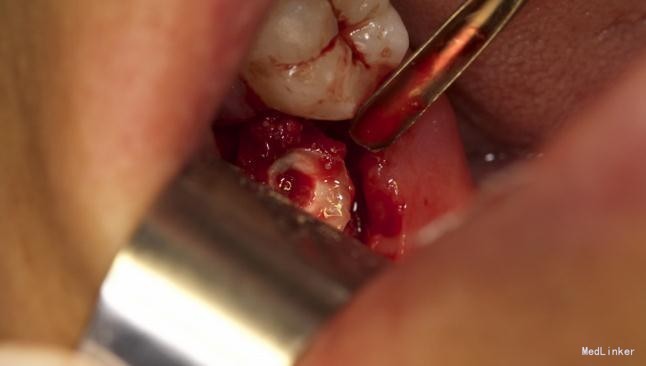

左下8水平阻生拔除

患者,男,25岁,要求拔除左下颌水平阻生牙齿,平素体质一般,无药物、食物过敏史,无高血压、心脏病等系统病史

拔除术